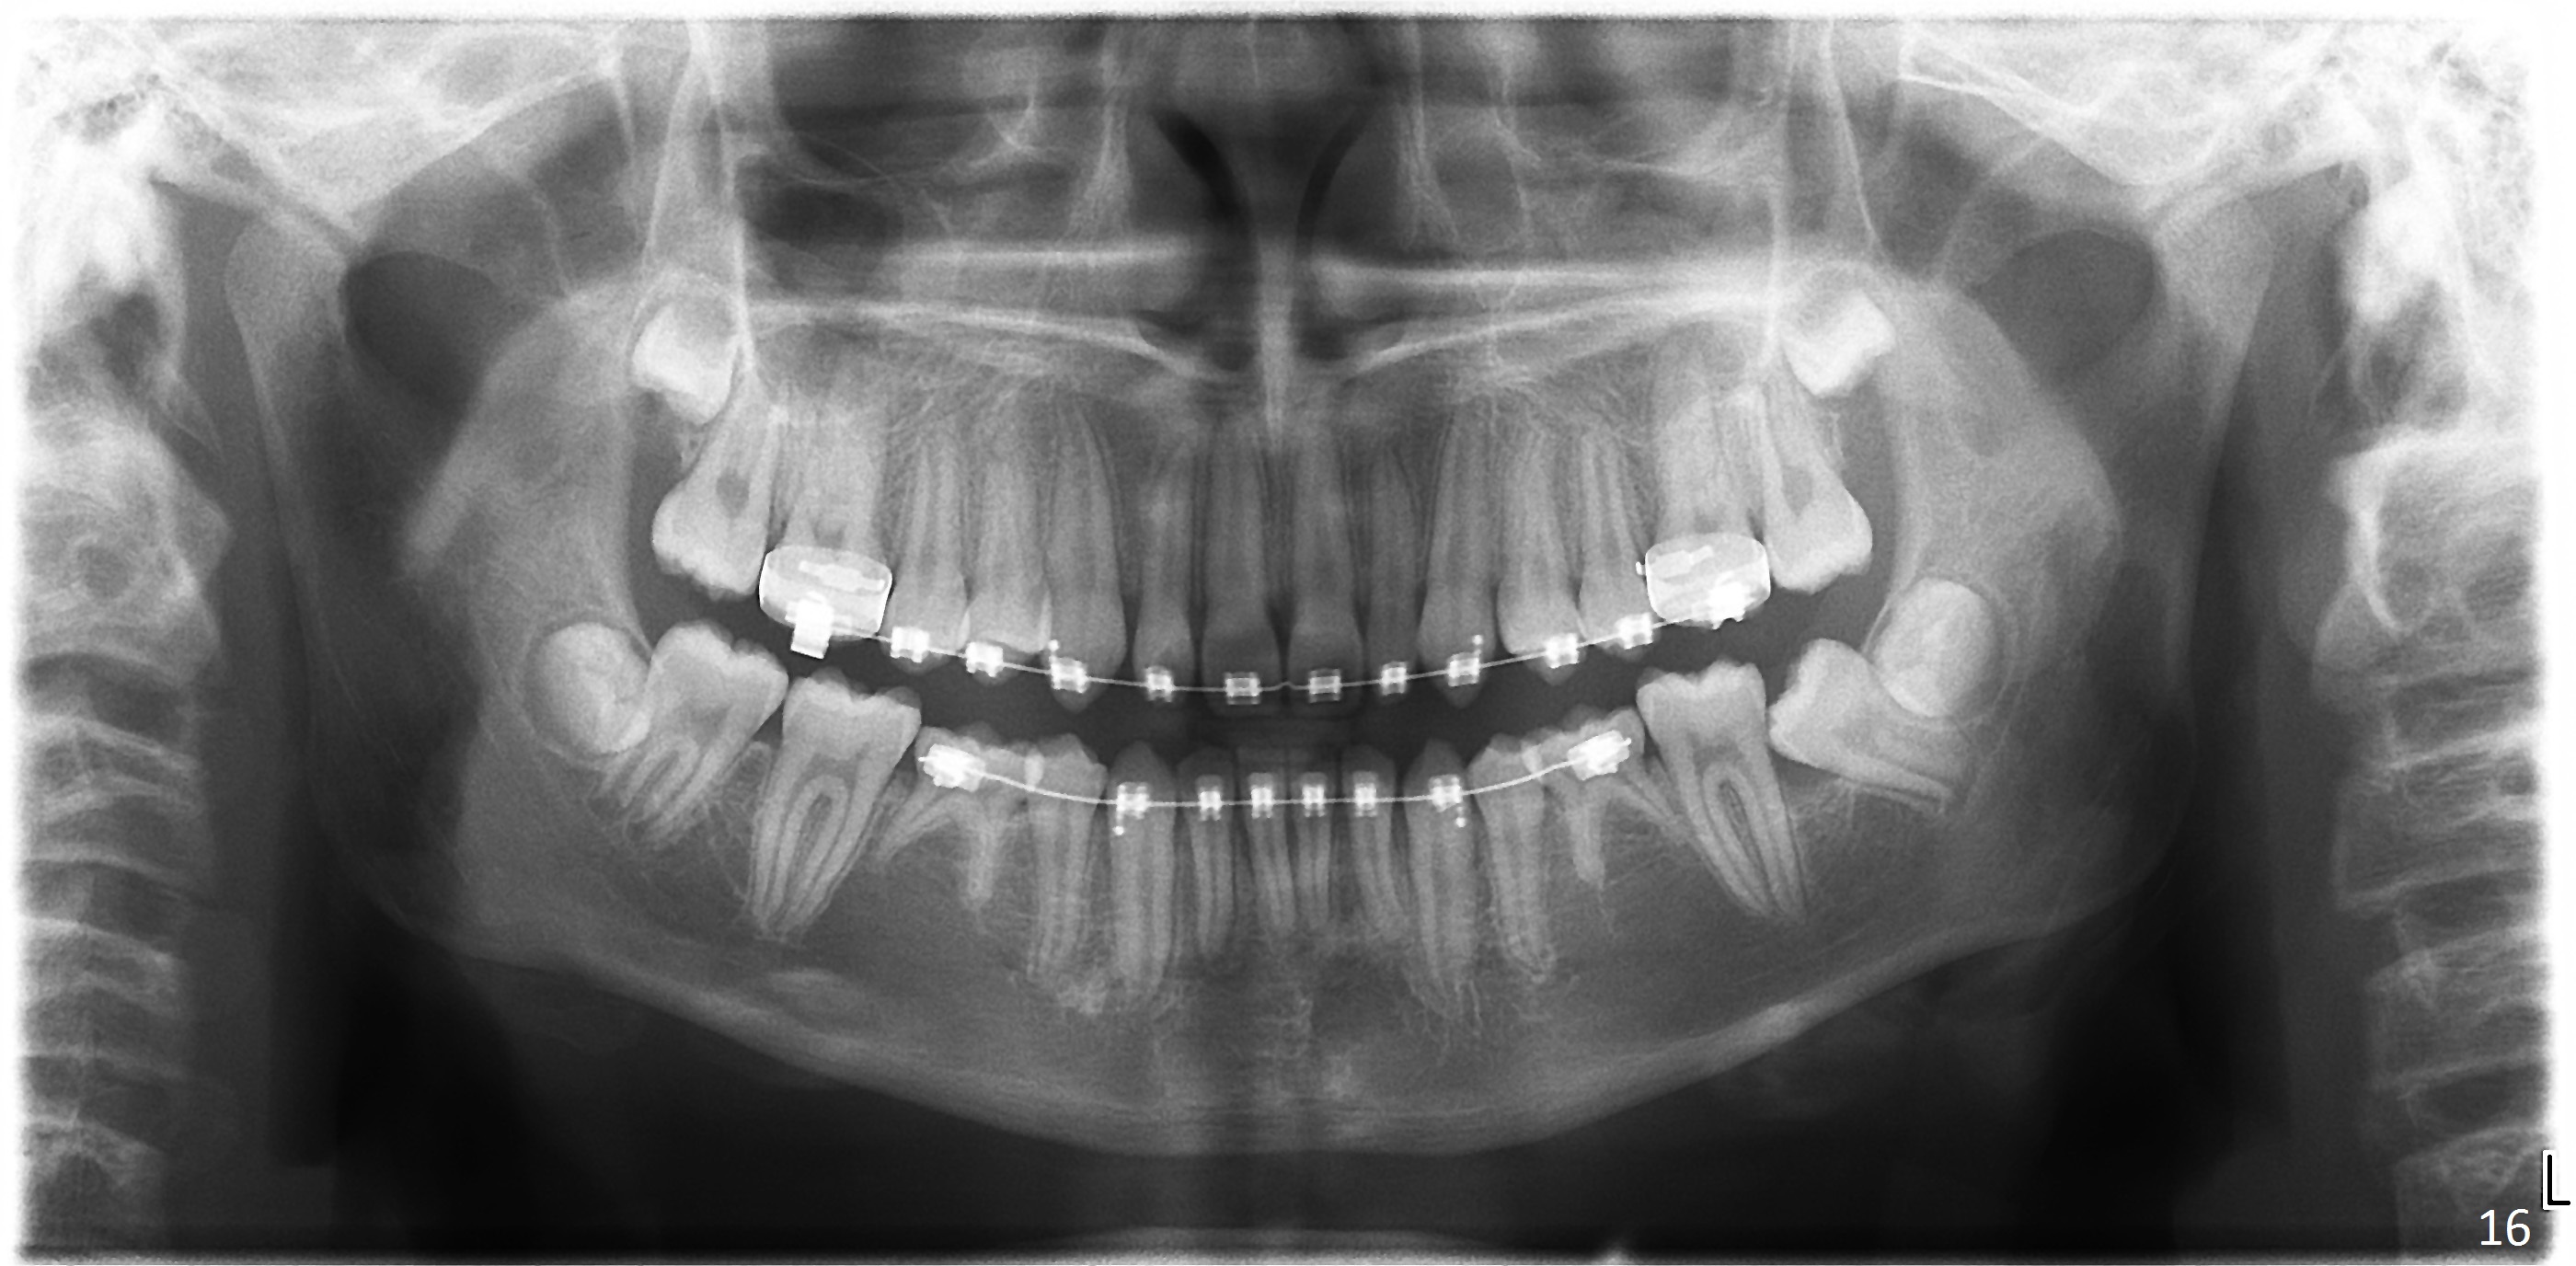

A 11-year-old boy has shorter lower 1/3 face (Fig.1,2) with light concave profile, especially the lower lip (Fig.3).  There is anterior deep bite (Fig.4) with Class II posterior occlusion (Fig.5,6).  UL2 is microdontia (Fig.7 *), while the Lower Es are retained (Fig.8).  Preop (2015_01_07) Ceph (Fig.9) and Pan (Fig.10) show ectopic L7s and congenitally missing L5s.

Brackets were placed on 2015_09_06 (Fig.11-13, Phase I pre-orthopedic tooth movement, leveling in advance of Herbst appliance therapy using ankylosed Es).   Six months later (Fig.14-16), LR7 did better, LL7 did not and will need intervention. But intrusion of L 3-3 looks good.